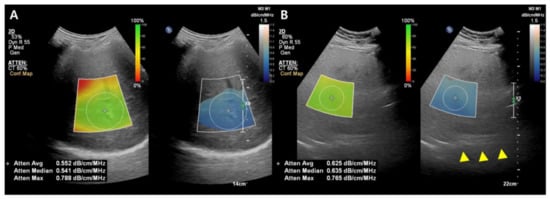

While the details of the evaluation method differ slightly between companies, the typical measurement process is as follows: (1) A convex probe is used to perform a B-mode US evaluation of the liver; (2) the probe is used to visualize the right hepatic lobe via an intercostal window for AC measurement; (3) the region of interest (ROI) is fixed in the right hepatic lobe at least 2 cm below the liver capsule to mitigate reverberation artifacts during breath-hold while excluding large vessels; and (4) the AC value (in dB/cm/MHz) and reliability of the measurement (in R2) are determined (Figure 3). A measurement of R2 ≥ 0.60–0.90 is considered satisfactory, and approximately five satisfactory measurements are used to assess hepatic steatosis. The technical failure rate for these methods, including ATI and UGAP, appears low (0–4.3%), although there is limited data available [36,38,39,40,41,42].

Figure 3.

Images from the attenuation coefficient (AC) from the Philips system (A,B). Mean AC value of image (B) (0.625 dB/cm/MHz) is higher than image (A) (0.552 dB/cm/MHz) which means a larger fat component in the image (B). The echo of the diaphragm is poorly visible (arrowhead). Confidence map is shown as a color box, and the poor-quality areas are not included in the measurement.

In various studies published recently, the AC calculated with these methods usually demonstrated a positive diagnostic performance for hepatic steatosis, with liver biopsy or MRI-PDFF as a reference standard [36,38,39,41,43,44]. The benefit of these methods over CAP is their employment of B-mode US images. Firstly, conventional US evaluation of the liver can be done at the same time as fat quantification. Secondly, the ROI for determining the AC can be placed during visualization of the liver, and a more dependable outcome can be determined by avoiding large vessels, ducts, and hepatic mass [36,38,39]. In a recent study, a quantitative US fat fraction estimator utilizing seven parameters (attenuation coefficient, backscatter coefficient, Lizzi-Feleppa slope, intercept, midband fit, and envelope statistics parameters k and µ) showed better accuracy than CAP in the diagnosis of hepatic steatosis in NAFLD patients [45].